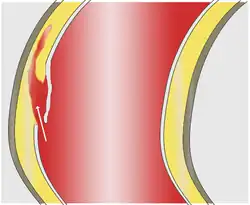

La dissection débute par une « porte d'entrée », rupture de la paroi interne (intima) permettant le décollement de cette dernière en pleine media (partie moyenne de la paroi). Ce décollement s'étend le plus souvent d'amont en aval et forme une poche de sang circulant, le « faux chenal », séparé du « vrai chenal » (la lumière de l'artère) par un flap (constitué par la paroi décollée). Plus rarement, la progression se fait en rétrograde : d'aval en amont (un tiers des cas[11]). La porte d'entrée peut être multiple dans un quart des cas[12].